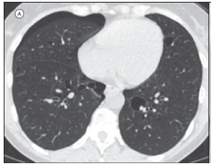

As imagens abaixo estão relacionadas a outras doenças pulmonares císticas.